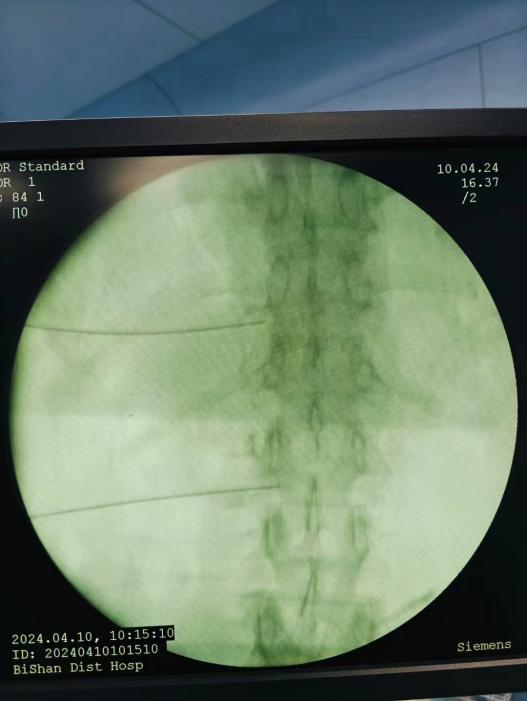

神經(jīng)阻滯,將藥物在影像引導(dǎo)下注射到受損神經(jīng)周圍,減輕炎癥和疼痛;

臭氧注射,通過向椎間盤內(nèi)注射臭氧,氧化髓核內(nèi)的蛋白多糖,降低椎間盤內(nèi)壓力,緩解癥狀;

射頻消融治療,連續(xù)射頻或脈沖射頻對椎間盤或神經(jīng)進(jìn)行干預(yù)治療,目的是減小神經(jīng)根周圍的壓力及對神經(jīng)的調(diào)控治療,從而達(dá)到緩解癥狀的效果;

膠原酶椎間盤化學(xué)溶解術(shù),是在影像引導(dǎo)下(C型臂X線機(jī)或CT),將膠原酶準(zhǔn)確地注射到突出的椎間盤內(nèi)及其周圍,使突出的椎間盤溶解并吸收,解除其對神經(jīng)根的壓迫,進(jìn)而緩解癥狀。